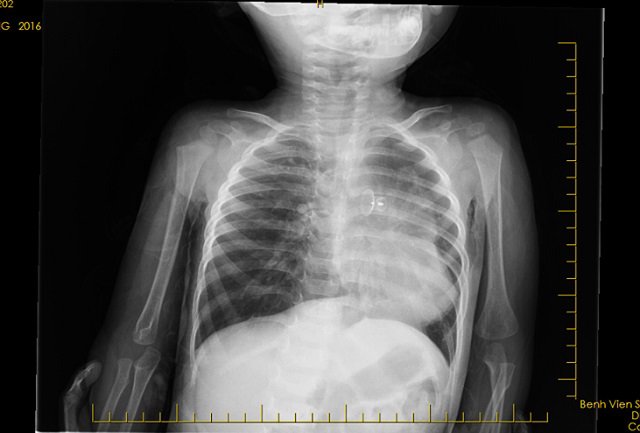

Hình ảnh phim chụp thấy rõ dị vật.

Kết quả chẩn đoán hình ảnh cho thấy, cháu D. có dị vật trong đường thở, gây tắc phế quản gốc phải. Sau đó, các bác sĩ đã chỉ định nội soi khí phế quản.